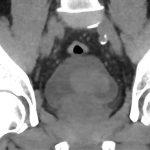

Η βιοψία προστάτη με τη χρήση της fusion τεχνολογίας αποτελεί μια νέα, πρωτοποριακή μέθοδο για τη διάγνωση του προστατικού καρκίνου. Αξιοποιεί τις πληροφορίες της mpMRI και επιτρέπει τη στοχευμένη βιοψία μέσω σύντηξης των τομών (mpMRI – U/S) σε πραγματικό χρόνο. Με αυτόν τον τρόπο, ο ιατρός έχει τη δυνατότητα να αναγνωρίσει τις «ύποπτες περιοχές» και να λάβει απολύτως στοχευμένα και με μεγάλη ακρίβεια, τις απαραίτητες βιοψίες από τις περιοχές αυτές.